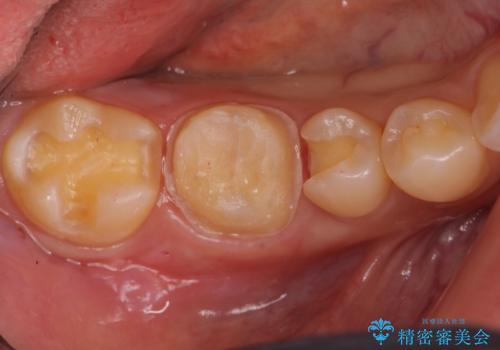

- 右下の保険治療での樹脂の劣化、および歯と歯の間の虫歯をセラミックのつめもので治療しました。

右下6番はセラミックのアンレーが入っていましたが、強度の問題もあり、やり直し後はクラウンとしました。